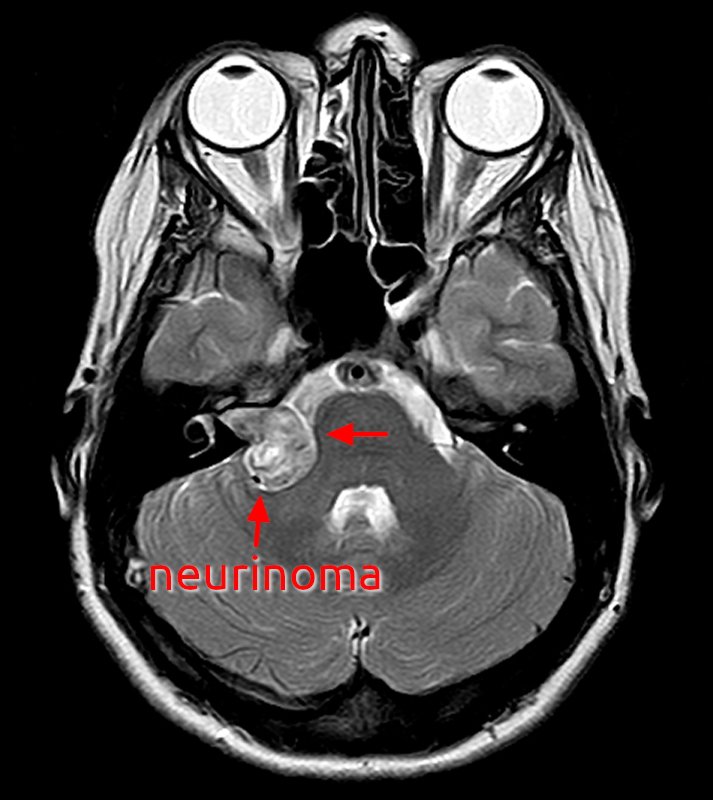

Neurinoma del nervo acustico

- Descrizione: Tumore del nervo uditivo. Originano dalla guaina di Schwann.